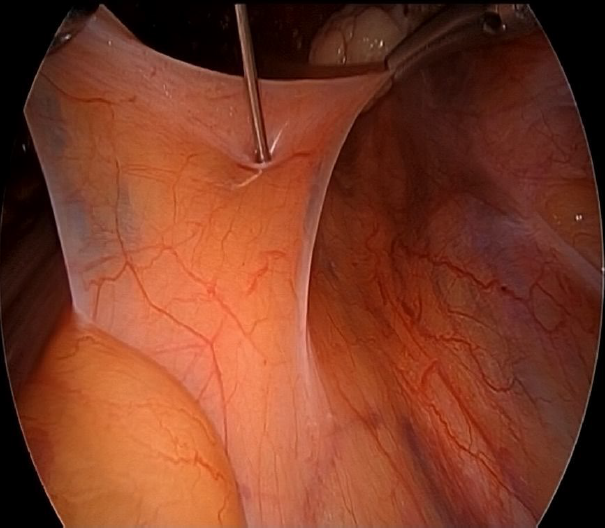

Two lateral 5 mm trocar and one 10 mm suprapubic trocar were needed in all of the procedures. Once the hysterectomy concluded, the patient remained in Lloyd-Davis position, the promontorium was located, and the surgeon managed to arrange the colon to the left in order to get a direct visión of the peritoneum. To administer the medication, two Croce Olmi forceps were used to grasp the peritoneum and tent it up (Figure 1), this way a laparoscopic needle was introduced through the central trocar loaded with ropivacaine 20 mL (0.2%) (Figure 2) and the anesthetic was infiltrated in the retroperitoneal space with the help of the forceps (Figure 3-4). After the withdrawal of the laparoscopic needle from the retroperitoneal space, the Croce Olmi forceps were used to keep the retroperitoneum tented and allow the anesthetic to properly infiltrate the retroperitoneal space (Figure 5). This procedure was performed under direct laparoscopic vision at the end of the surgical procedure, right before the withdrawal of the laparoscopic instruments. This was done with the intention of not letting the surgical time be a biased element that may vary from patient to patient, decreasing the anesthetic effect during the post-surgical period. The anesthetic was successfully administered in all of the patients in the SHP group. There were no immediate complications reported in any of the procedures. Table 1. Medications and doses used to induce general anesthesia and additional medications administered by the anesthesiology team.

Figure 1. Using a grasper and a Maryland instrument to tent up the retroperitoneum.